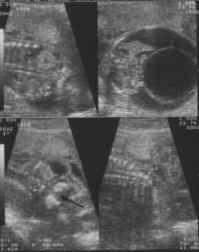

- Coupe sagittale :

Solution de continuité ou tuméfaction du revêtement cutané et des parties molles :

Hernie méningée remplie de LCS , faisant saillie en arrière du rachis, anéchogène, généralement à paroi fine parcourue par des travées neurologiques, échogènes, distribuées de façon linéaire ou anarchique avec placode neurale possible sur la paroi herniaire (cliché 4).

Canal rachidien se jetant dans la hernie à large canal.

Lames latérales irrégulièrement disposées sur une coupe parasagittale.

- Coupes transversales :

Ouverture des lames postérieures +/- marquées : Aspects classiquement décrits en U, en V ou en cupule (spina plan) selon le redressement ou la pergence des lames postérieures.

Visibilité des cloisons dans la hernie méningée confirmant le diagnostic de myélo-méningocèle.

- Coupes frontales :

Ecartement des lames postérieures responsables de la perte de parallélisme du "rail spinal".

Affleurement et renflement anormal du canal rachidien qui perd son caractère linéaire (collet herniaire).

En dehors du rachis, tuméfaction (hernie) mobile avec le foetus.